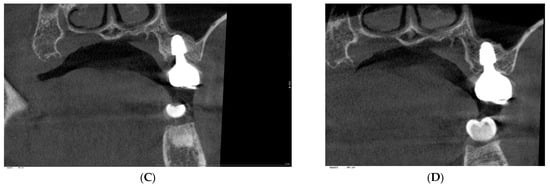

Background: Subcrestally placed implants (SPIs) present advantages for bone preservation and soft tissue support but pose challenges in maintaining peri-implant soft tissue health. This case explores the role of Crest to Restoration Distance (CRD) in the development and resolution of peri-implant mucositis. Case Presentation: A 57-year-old woman received two SPIs—one in the upper left and one in the lower right first molar region. Despite similar implant systems and prosthetic protocols, the upper left implant developed mucositis, characterized by bleeding on probing and discomfort, while the lower right implant remained stable. Three-dimensional analysis using cone-beam computed tomography (CBCT) revealed excessive CRD at the affected site. Results: After prosthodontic revision to reduce the CRD, clinical signs of mucositis resolved, with probing depths reduced to less than 1 mm and no bleeding on probing. The control site remained healthy throughout the observation period. Practical Implications: This case highlights CRD as a modifiable prosthetic factor influencing soft tissue stability. A three-zone model—comprising the sulcus, transitional zone (TZ), and subcrestal zone (SZ)—is introduced to provide a biologically grounded framework for understanding soft tissue adaptation around SPIs. Full article